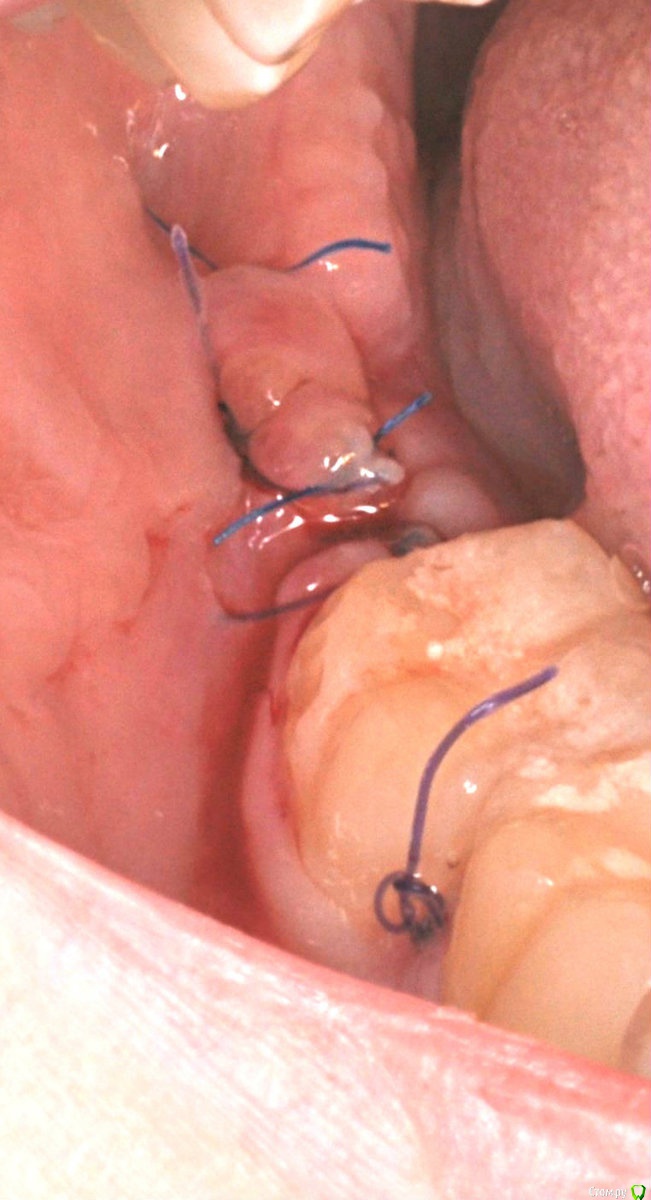

колесников Опубликовано 1 апреля, 2017 Автор Поделиться Опубликовано 1 апреля, 2017 Из свежего Ссылка на комментарий

колесников Опубликовано 2 апреля, 2017 Автор Поделиться Опубликовано 2 апреля, 2017 Тройной лоскут , вид через 5 -7дней. Снимок "до". И благодарность за скорое заживление 6 Ссылка на комментарий